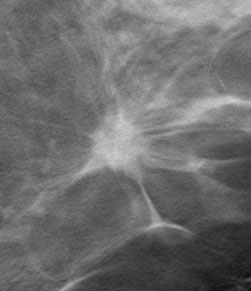

Invasive Ductal Carcinoma on digital mammogram (above left) and digital tomosynthesis (above right). Digital tomosynthesis shows clear presence of a spiculated mass.